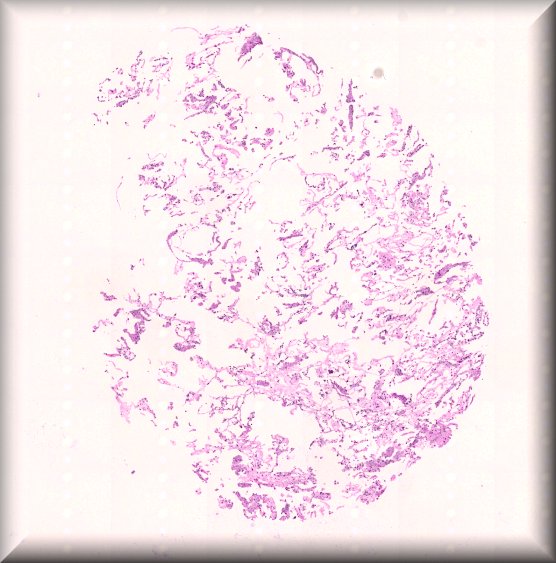

Susan Kennedy: Exenteration specimen of a 70-year-old female who underwent multiple (14) surgeries for conjunctival melanoma over a period of two years. |